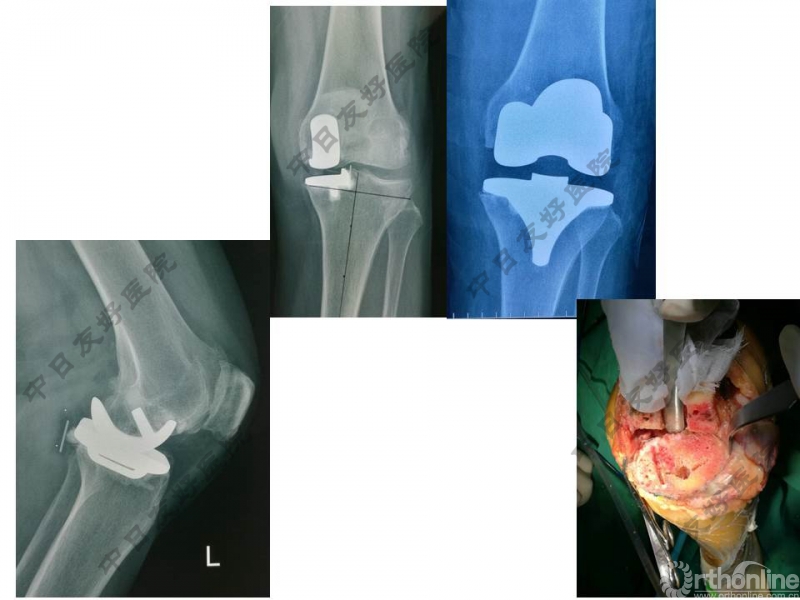

本期我们为大家带来本次研讨会上中日友好医院骨关节外科郭万首教授关于“OUKA手术技术原则与要点”的专题讲座视频。